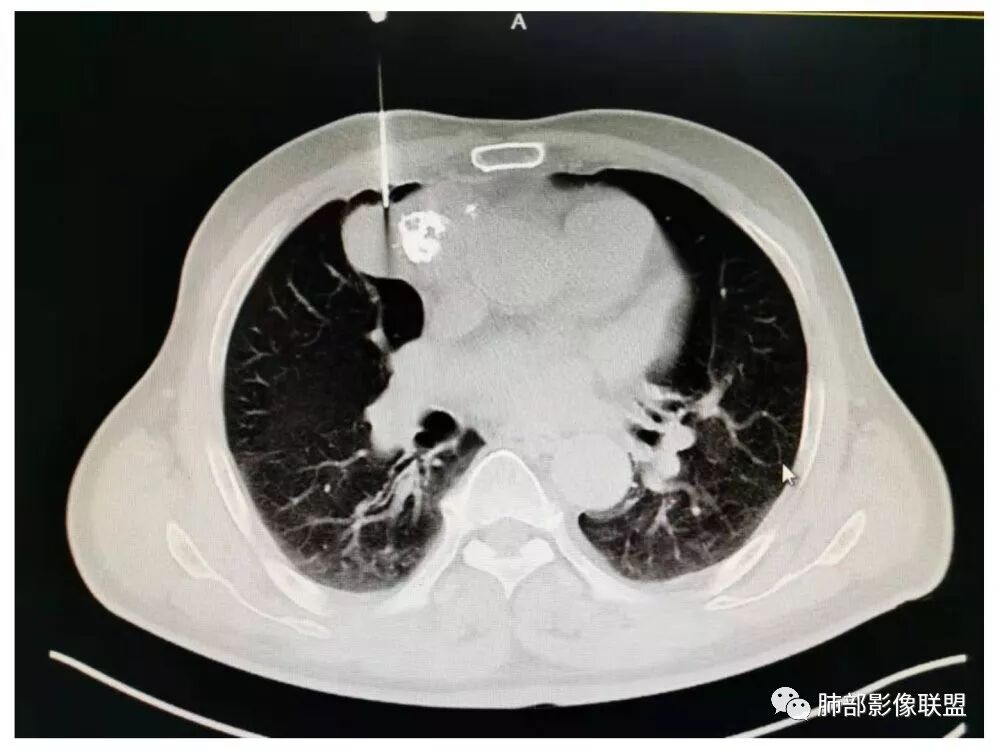

水晶石头:患者老年男性,发现皮肤粘膜黄染5天,右肺占位1天。

胸部CT:右肺中叶内侧段紧邻心脏实性结节,边缘光滑,边界清楚,宽基底与胸膜相连,内可见不规则钙化,钙化内见点状低密度影,增强中度强化,综合考虑良性病变。畸胎瘤可能大,鉴别胸膜孤立性纤维瘤及胸腺瘤。

王秀仙:右侧前纵隔肿块,边缘分叶,周围肺组织推移,宽基底与纵隔胸膜相连,可见胸膜尾征,密度不均,病灶中心可见斑块状钙化,右侧内乳动脉位于病灶前外侧并略增粗,实性成分明显强化,考虑纵隔畸胎瘤,鉴别胸腺瘤。

蓝天白云:定位纵隔,病灶呈实性成分,内见钙化,钙化位于病灶中心,实性成分均匀延迟强化,考虑良性病变,如果胸膜起源考虑sft,纵隔来源胸腺瘤,鉴别畸胎瘤。黄勇老师说过右侧心膈角区可以发生胸腺瘤

右侧前纵膈肿块,边缘分叶,病灶中心可见斑块状钙化,实性成分明显持续强化,考虑胸腺瘤。